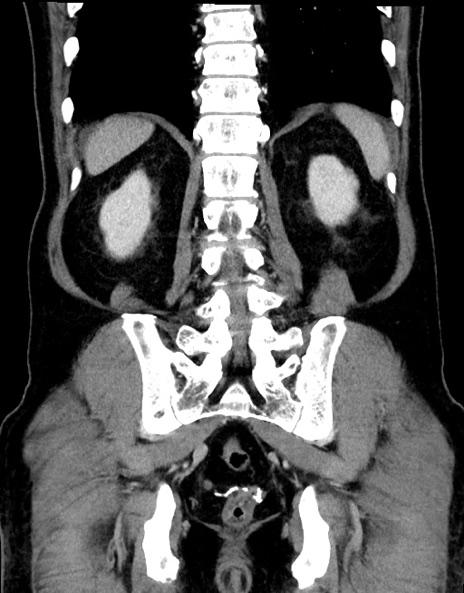

症例15(冠状断像)

【症例】70歳代男性

【主訴】腹痛

【現病歴】今朝から腹痛あり。全体的に痛い。特に左上の方。排ガスが今日はない。冷や汗が出る。

【既往歴】直腸癌術後

【身体所見】左側腹部〜上腹部に圧痛あり。腹膜刺激症状明らかなではない。軽度反跳痛。左下腹部に術後瘢痕あり。

【データ】WBC 7700、CRP 0.02